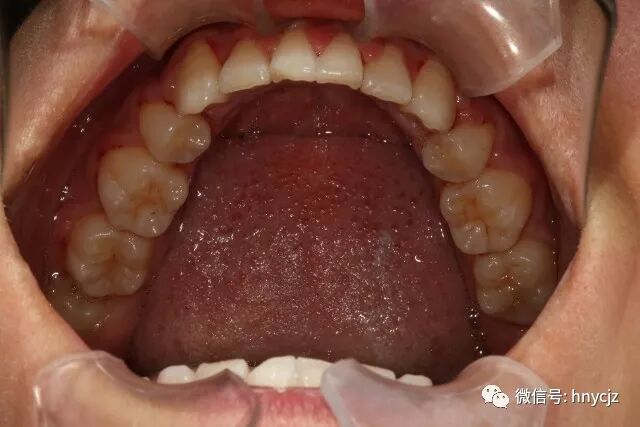

我选择了在自己生活的地方长沙做,在几家医院中挑选了下,最后选了长沙牙大夫口腔。我的主治医生是崔医生,给我的方案是全口矫正,扩弓调整弓形,排齐牙齿,耗时2年,今年3月11号拆除矫正器,已经戴保持器一个多月了,目前正美美的度着五一假。

牙齿也变得越来越整齐